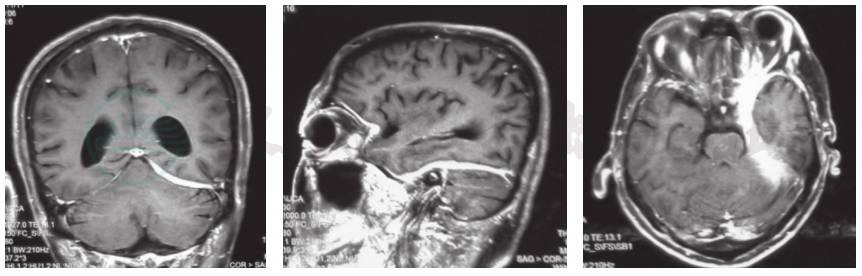

入院后完善辅助检查,血常规白细胞计数13.40×109/L,中性粒细胞比例87%;肝功能试验血清谷丙转氨酶282U/L,谷草转氨酶190U/L;尿沉渣24小时尿蛋白定量0.52g,红细胞潜血25个/μl,红细胞计数9.70个/μl;尿常规、粪便常规、肾功能试验、电解质和凝血功能均于正常值范围;感染相关检测,结核菌素纯蛋白衍生物(PPD)、血清结核感染T细胞斑点试验(T-SPOT.TB)、血清巨细胞病毒(CMV)/EB病毒(EBV)DNA、感染免疫检测四项均呈阴性,2次痰培养均呈阴性,包括细菌和真菌培养、奴卡菌涂片、抗酸染色、六胺银(PASM)染色、墨汁染色、结核分枝杆菌(TB)/非结核分枝杆菌(NTM)DNA均呈阴性;免疫相关检测,红细胞沉降率(ESR)>140mm/h、超敏C反应蛋白(hsCRP)158.95mg/L(0~3mg/L),血清抗中性粒细胞胞质抗体(ANCA)IgG型免疫荧光法(IFA)呈阳性(<1:10)、髓过氧化物酶型 ANCA(MPO-ANCA)137RU/ml(<20RU/ml),抗核抗体(ANA)谱、抗可提取性核抗原(ENA)抗体、类风湿性关节炎(RA)相关自身抗体谱均于正常值范围,血清IgG及其亚型(IgG1、IgG2、IgG3、IgG4)于正常值范围。腰椎穿刺脑脊液外观清亮、透明,压力58mmH2O,细胞总数28×106/L、白细胞计数22×106/L、单核细胞计数22×106/L,蛋白定量980mg/L、葡萄糖和氯化物于正常值范围;病原学筛查呈阴性,包括细菌涂片和培养、真菌涂片、奴卡菌涂片和培养、墨汁染色、抗酸染色、结核分枝杆菌/非结核分枝杆菌DNA测定、梅毒螺旋体明胶凝集试验(TPPA)和快速血浆反应素试验(RPR)、EB病毒衣壳抗原IgM(VCA IgM)、布鲁氏菌虎红试验、隐球菌抗原测定、抗莱姆病抗体、脑囊虫抗体均呈阴性;脑脊液细胞学检查白细胞计数1000/0.50ml、淋巴细胞比例0.90,呈淋巴细胞性炎症反应;寡克隆区带(OB)和副肿瘤相关抗体(抗Hu、Yo、Ri抗体等)于正常值范围。影像学检查:头部MRI增强扫描(2017年11月11日)显示左侧海绵窦、小脑幕和颅底硬脑膜增厚伴强化征象(图1),考虑炎症性病变可能性大。PET/CT显示右侧肺尖斑片影,代谢稍增高,双肺支气管血管束走行区多发代谢增高,考虑炎症性病变。胸部增强CT和高分辨率CT(HRCT)显示双肺支气管血管束增粗,支气管壁多发増厚,双肺散在索条影,右肺下叶钙化点,双侧肺门和纵隔多发小淋巴结,部分钙化。眼眶CT未见明显异常。

图1 患者治疗前头部MRI检查

a.冠状位增强T1WI显示左侧小脑幕和颅底硬脑膜增厚伴强化征象;b.矢状位增强T1WI显示硬脑膜广泛性增厚伴线性强化征象;c.横断面增强T1WI显示左侧海绵窦、颞区硬脑膜增厚伴强化征象